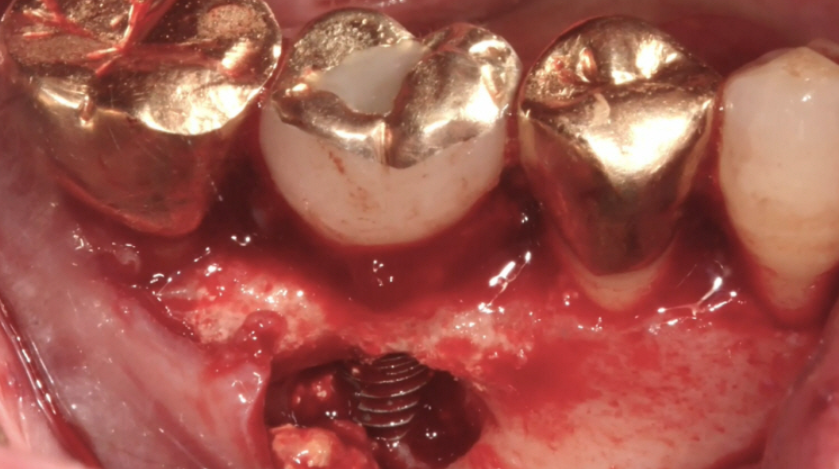

국소 마취 후 잇몸 절개와 연조직 박리를 거쳐 임플란트를 식립하고 피개 나사를 장착합니다. 평균 성공률은 약 95%이며, 환자의 상태에 따라 결과가 달라질 수 있습니다. 예상 소요 시간은 한 개당 20-30분 정도지만 추가적인 골이식이나 상악동 거상술 등이 필요한 경우 시간이 더 걸릴 수 있습니다.

임플란트를 심은 기둥 주변의 잇몸뼈 조직에 염증이 발생하는 질환으로, 잇몸이 붓고 아프며, 악취가 나고 고름이 생길 수 있습니다. 장기간 방치할 경우 잇몸뼈가 소실되어 임플란트가 흔들리거나 빠질 위험이 있습니다. 임플란트를 심은 후 잇몸을 제대로 관리하지 않는 것이 주요 원인입니다. 임플란트 주변에 남아 있는 음식물 찌꺼기와 치석이 제거되지 않아 세균이 번식하면서 염증이 발생합니다. 흡연 또한 임플란트 주위염과 잇몸뼈 손실을 초래할 수 있습니다.